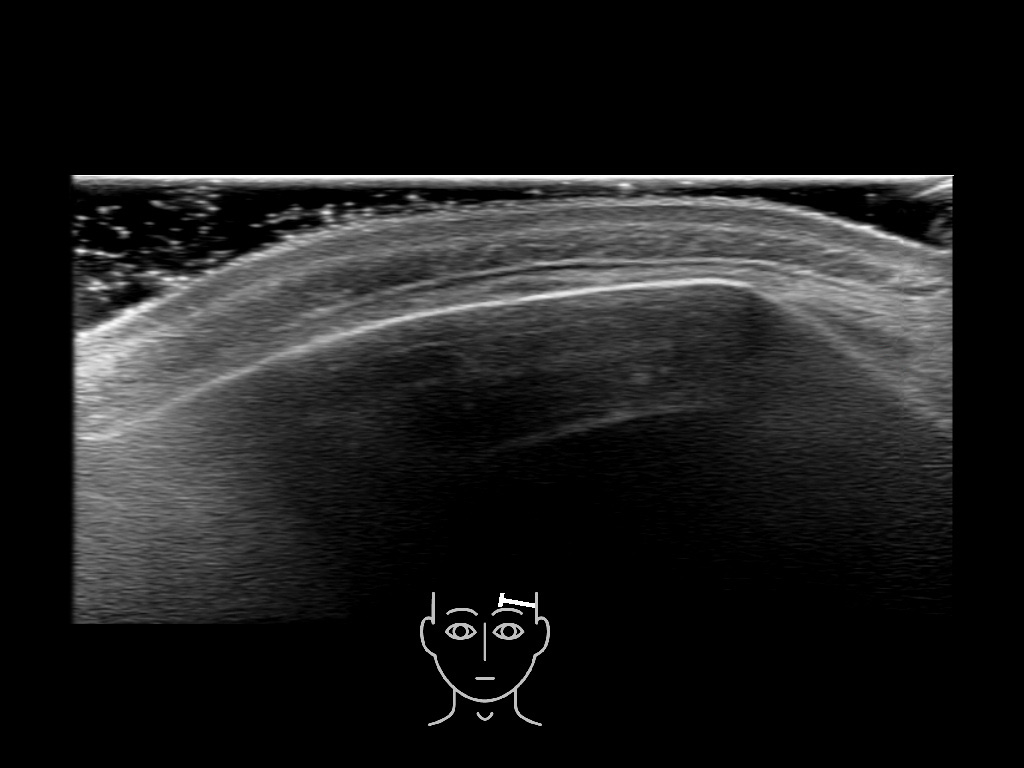

In this section you will learn more about the different layers of the face with the use of ultrasound. When you click on the secondary ultrasound image, you will see the different structures as an overlay. This will help to train yourself to recognize the different layers of the face.

Study the first image to recognize the different layers. If you are sure about the layers, swipe to the second image to view the answer (if applicable).